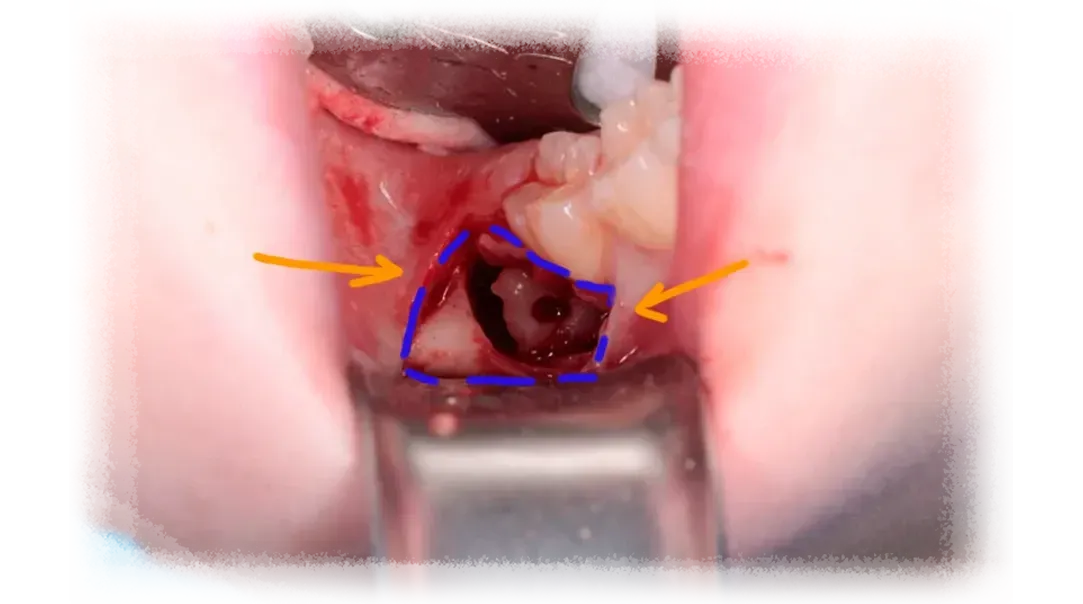

In many situations, yes. A large number of third molar extractions are referred simply because the process of evaluating case difficulty and planning the surgery isn't always clearly taught.